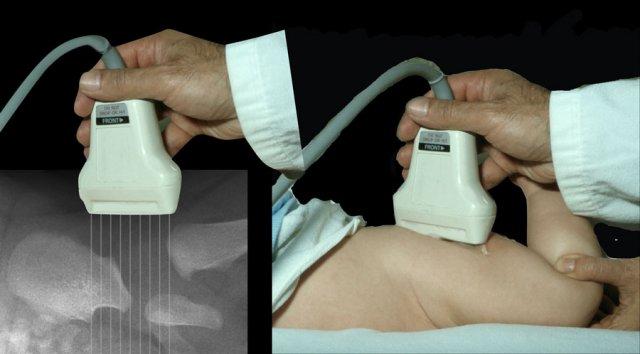

Sử dụng đầu dò tần số cao tuyến tính.

Tiêu điểm được đặt tại bờ ổ cối.

Điều quan trọng là phải hiển thị hình ảnh trên mặt phẳng vành (coronal) ở mức sụn tam diện (triradiate cartilage), đây là khớp sụn (synchondrosis) giữa xương chậu, xương ngồi và xương mu tạo nên ổ cối.

This is shown in the video.

Instability

Đôi khi trong các trường hợp loạn sản khớp háng nặng, việc sử dụng đầu dò lồi có thể hữu ích.